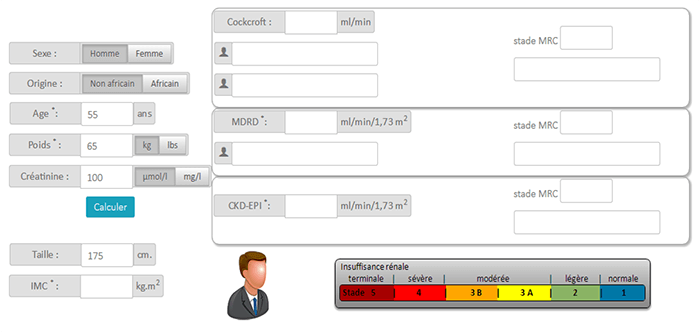

Estimation of Clearance for Adults

When radiographic contrast media are injected intravenously or intra-arterially, they pass from the vascular compartment through capillaries into the extracellular space. They are eliminated almost entirely by glomerular filtration, concentrated in the tubular lumen by water tubular reabsorption, thereby visualizing the urinary tract. But the measurement of creatinine clearance, as derived from 24-hour urine collection, is a cumbersome, impractical, and inaccurate test. The estimated glomerular filtration rate (eGFR) is more accurate and significantly easier to obtain.

- If the clearance reaches 50 ml/min, we can explain to the patient that his kidneys are functioning at 50% of their capacity

- With a clearance of 10 ml/min, replacement therapy has to be considered such as dialysis or a kidney transplant

MDRD Formula

MDRD or Modification of Diet in Renal Disease estimates the glomerular filtration rate (GRF) based on creatinine and patient characteristics.

- If male = 186.3 x (creatinemia in (μmol/L) / 88.4)(-1.154) x age-0.203

- If female = 186.3 x (creatinemia in (μmol/L) / 88.4)(-1.154) x age-0.203 x 0.742

- Black race = Result x 1.212

Benefits of the MDRD equation

- A patient’s weight is not necessary. GFR can be calculated from serum creatinine

- GFR estimation is more reliable in the case of older patients

- The international classification of kidney disease is based on the results of the MDRD

Patients with Renal Failure

Clearance is considered to be the amount of liquid filtered out of the blood that gets processed by the kidneys. For kidneys, it is expressed in ml/min.

- The calculation of clearance is important before injection to avoid possible nephropathy induced by iodinated contrast agents

- In the case of CT injection, renal clearance will be the time required to remove the iodinated contrast agent per unit time

Nephropathy

Depending on the Glomerular Filtration Rate (expressed in ml/min/1,73m2), we can distinguish 5 stages for the kidney function condition. For children and elderly patients, the clearance is low therefore it is very important to perform an analysis on a blood sample before injecting any contrast agent.